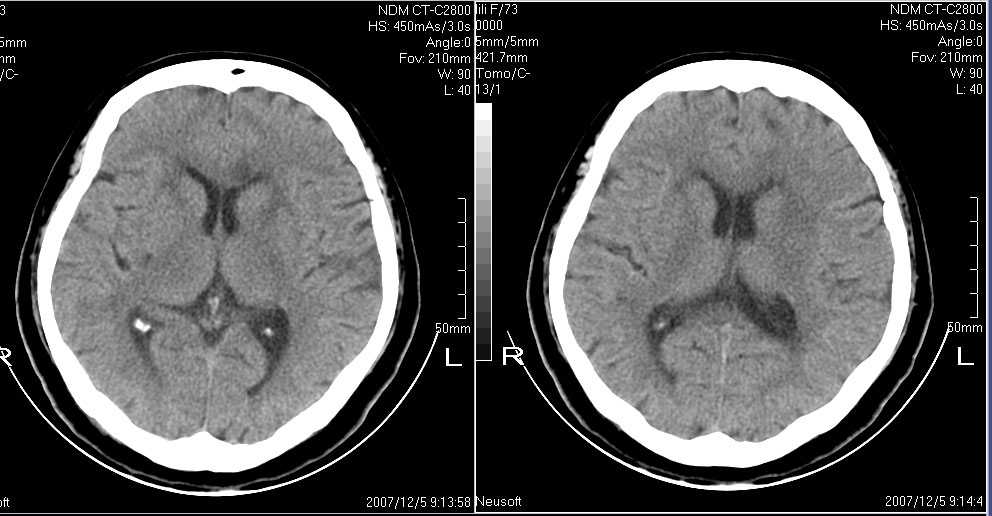

女,72,有高血压病史,突然寡言少语3日.

双侧基底节、胼胝体膝部多发腔隙性脑梗塞。

双侧基底节、左侧额叶 胼胝体膝部多发腔隙性脑梗塞。

1左额叶梗塞(多有情感障碍)2皮层下动脉硬化症